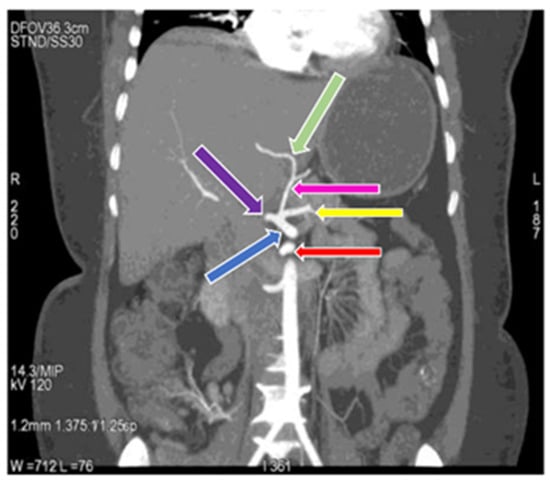

3.1. Variation in Origin and Branching Pattern of Celiac Trunk

3.2. Variation in Origin and Branching Pattern of Hepatic Artery